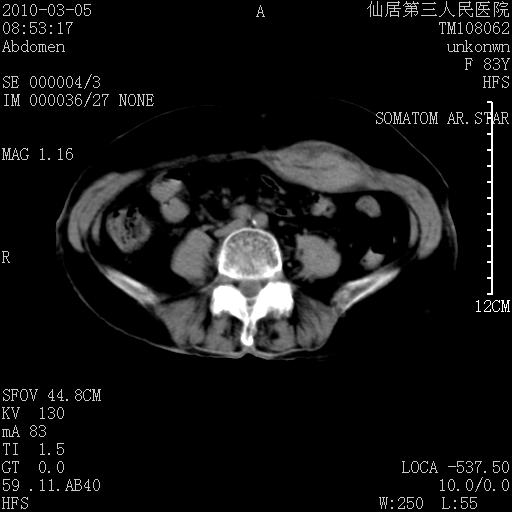

标题: CT24879:腹直肌病变。在线等。 [打印本页]

标题: CT24879:腹直肌病变。在线等。

女性,83y,腹痛一周。

考虑:左侧腹直肌神经纤维瘤可能

神经纤维瘤—伴有出血?

有无外伤,血肿或韧带样瘤

考虑左侧腹直肌血肿,肿瘤性病变待排。

增强看看,mfh可能性大,次之可考虑血肿、bfh、转移瘤、神经纤维瘤、侵袭性韧带样纤维瘤等。肝内钙化灶,右肾结石。

支持血肿

支持腹壁纤维肉瘤

血肿,纤维瘤,子宫内膜异位都有可能。